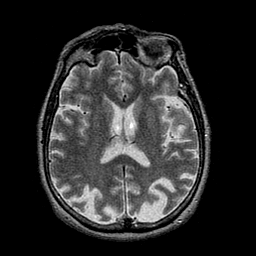

Alzheimer's disease: overlay -- Slice #30

[Home][Help][Clinical] Slice 30